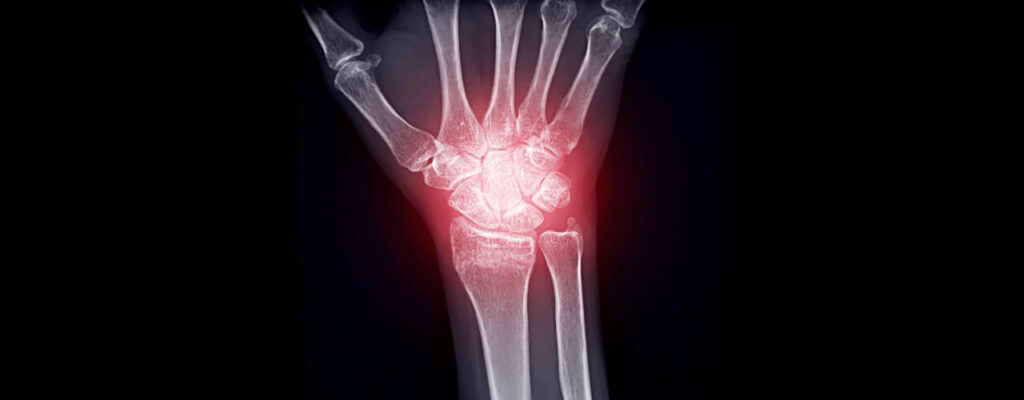

How to Manage Joint Inflammation from Arthritis

Linda’s arthritis had progressed over the years, making simple tasks like opening jars or climbing stairs feel monumental. The swelling in her knees and hands made her joints stiff and sore, and the pain seemed to flare up unpredictably.